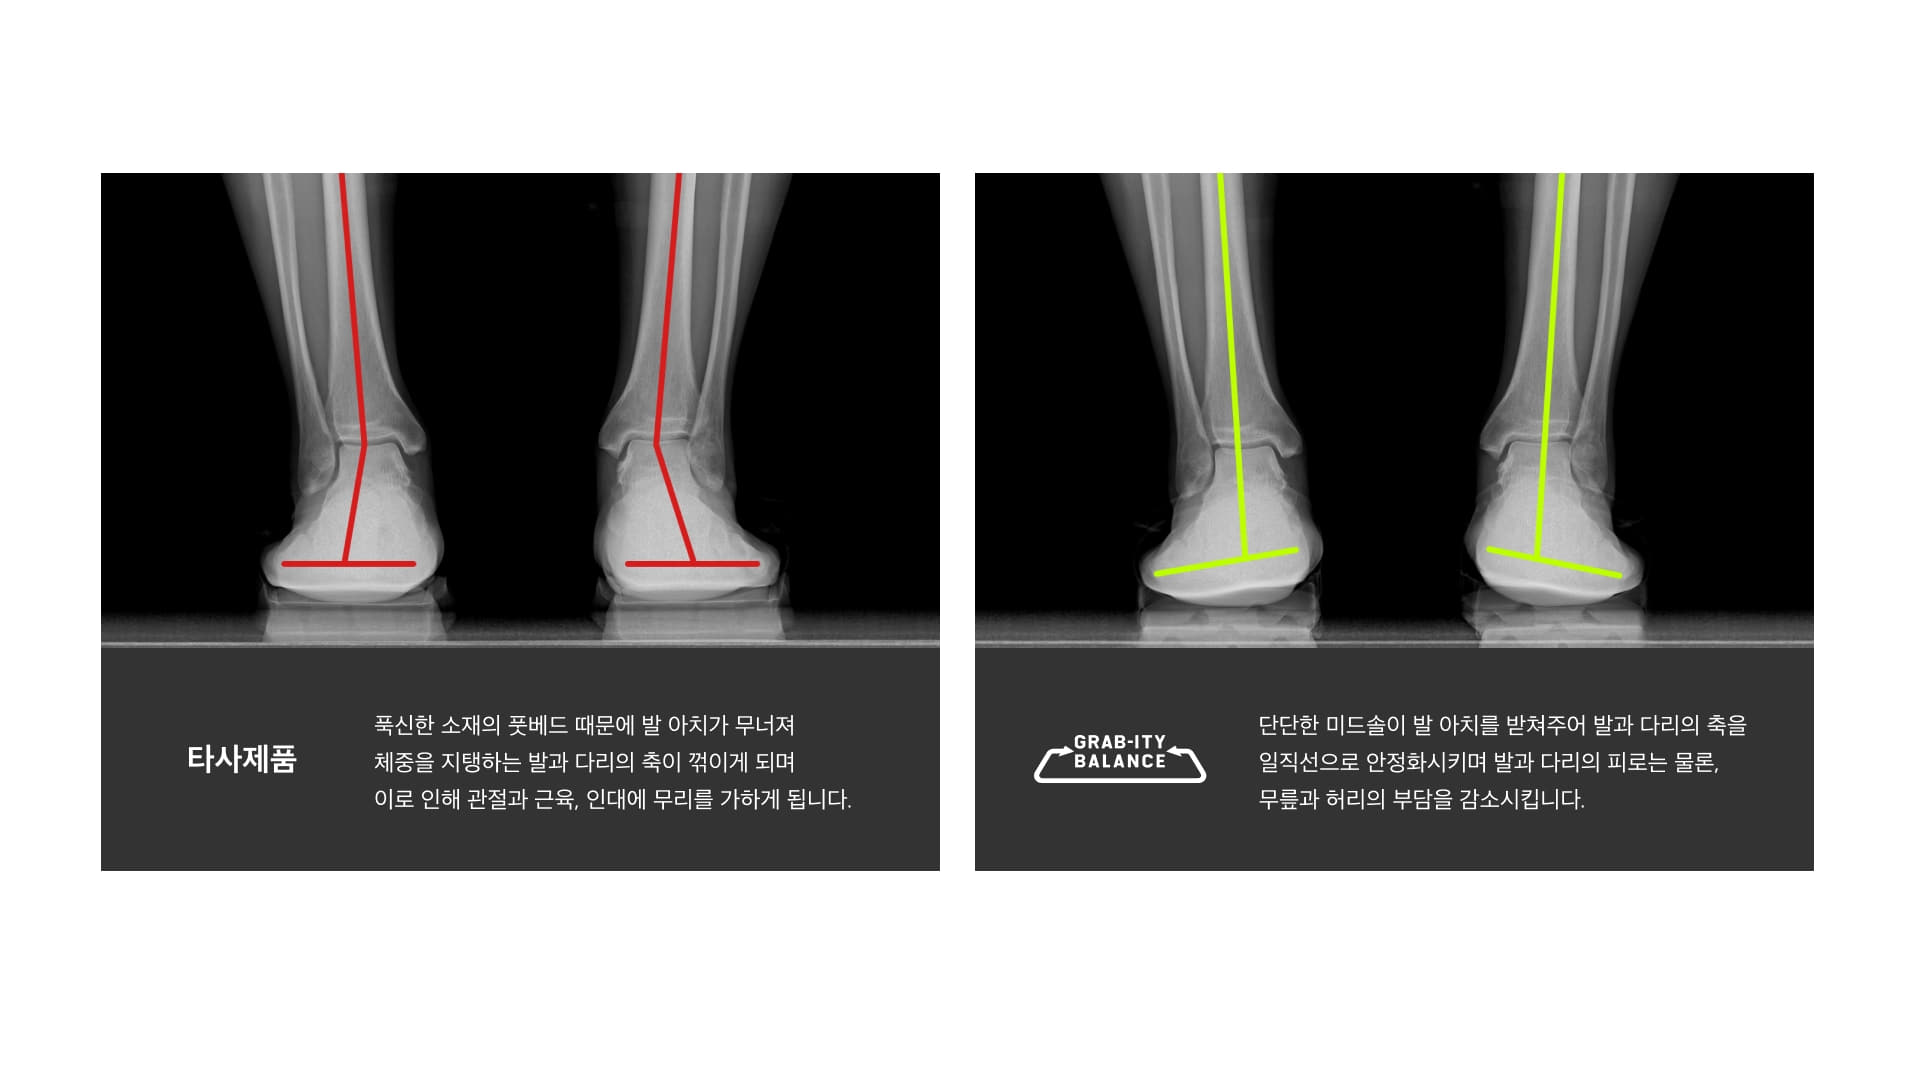

부드러운 미드솔과 단단한 아웃솔의 개념을 뒤집어서 아치를 받쳐주고 힐을 잡아주는 단단한 미드솔과 지면의 충격을 완화하는 부드러운 아웃솔로 상식을 뒤집는 2중 구조를 개발 합니다. 이 새로운 조합은 무릅과 골반의 하중부담을 분산시켜 신체 밸런스 향상과 몸의 피로회복에 도움을 준다고 합니다.